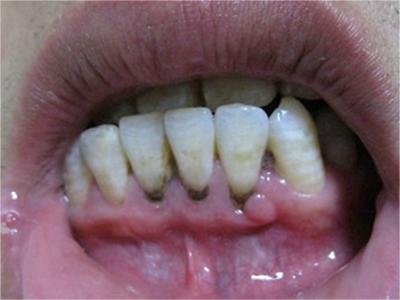

牙龈炎是发生于牙龈组织的炎症,患者可出现牙龈出血伴肿胀、发红、正常形态改变和偶尔不适等症状。本病主要由口腔卫生状况差导致,包括口腔不洁、牙菌斑等,诊断依据临床检查,治疗包括专业牙齿清洁和加强家庭口腔卫生。

牙龈炎可先引起牙齿与牙龈之间的沟(龈沟)加深,然后牙龈充血,炎症围绕一个或多个牙齿,伴牙龈乳头肿胀和易出血。一般无痛,可自行消退,也可维持轻度炎症数年。

牙龈炎常见的病因是口腔卫生差,不良的口腔卫生使牙菌斑沉积于牙齿与牙龈之间,造成龈沟加深,另外牙结石、不良修复体等也可造成牙龈炎的发生。